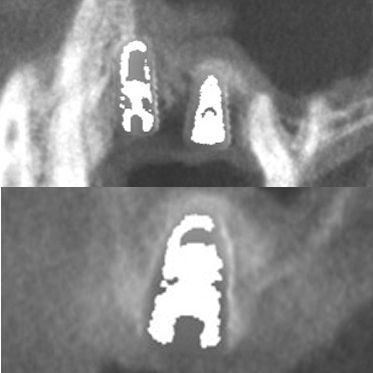

● 上の顎の奥歯にインプラントを入れるのに骨が足りないため、ソケットリフトと人工骨補填して骨造成を行った症例1

術前

藤沢デンタルオフィスのインプラント術前 藤沢デンタルオフィスのインプラント術前

3Dシミュレーション

術後

藤沢デンタルオフィスのインプラント術後 藤沢デンタルオフィスのインプラント術後

シミュレーション通りの上顎洞底挙上と人工骨補填(3Dガイドシステム使用)

● 上の顎の奥歯にインプラントを入れるのに骨が足りないため、ソケットリフトと人工骨補填して骨造成を行った症例2